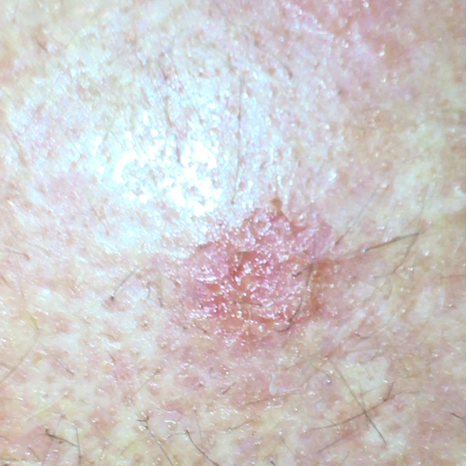

A queratose actínica geralmente torna a pele de cor marrom-avermelhada com áreas elevadas e uma superfície áspera e crocante. Isso ocorre porque a tradução literal de queratose actínica significa cornificação da pele induzida pelo sol. A crosta geralmente é branca, mas também pode ser amarela ou marrom. As manchas geralmente têm de alguns milímetros a centímetros de tamanho. Em geral, não apresentam sintomas, às vezes uma sensação de incômodo ou coceira. Essa anormalidade cutânea é frequentemente observada na face, nas costas das mãos, nos braços, nas pernas, no decote, no pavilhão auricular ou, em homens calvos, no couro cabeludo. Geralmente, há várias QAs na pele.

Exemplo de foto de queratose actínica